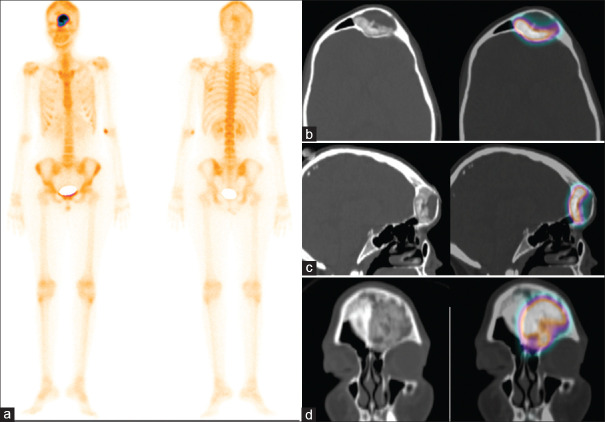

Giovane donna di 22 anni con massa frontale sinistra in lento e progressivo accrescimento da 8 anni. Presenta sintomi locali (arrossamento oculare, algie, cefalea) in assenza di deficit visivi. È stata eseguita una scintigrafia ossea con 99mTc-MDP.

Le immagini tardive (a) hanno mostrato una focale ed intensa captazione del tracciante nel cranio, in corrispondenza del margine sovraorbitario sinistro. Le immagini SPECT-TC nelle sezioni assiale (b), sagittale (c) e coronale (d) hanno evidenziato un’opacità a “vetro smerigliato” che coinvolgeva il margine posteriore del seno frontale sinistro, apparso ingrandito. La scintigrafia ossea ha documentato un quadro di displasia fibrosa monostotica.